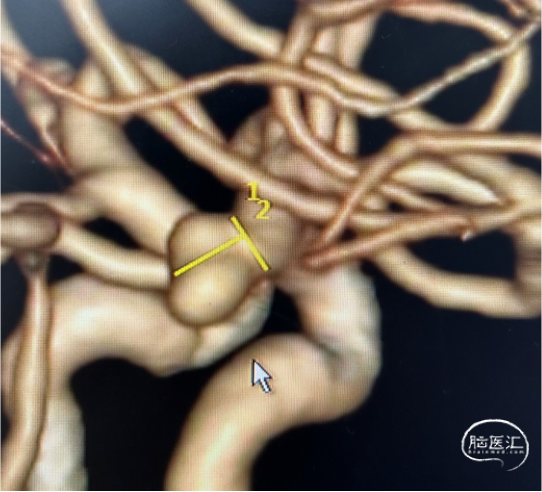

微导管3D评估动脉瘤与载瘤动脉关系

WEB选择:理想SL9x3(没有),选择SL8x4

直接测量:7.4x3.92mm

3D测量:7.22x5.35mm

对比测量:8.9x4.8mm(偏大10%)